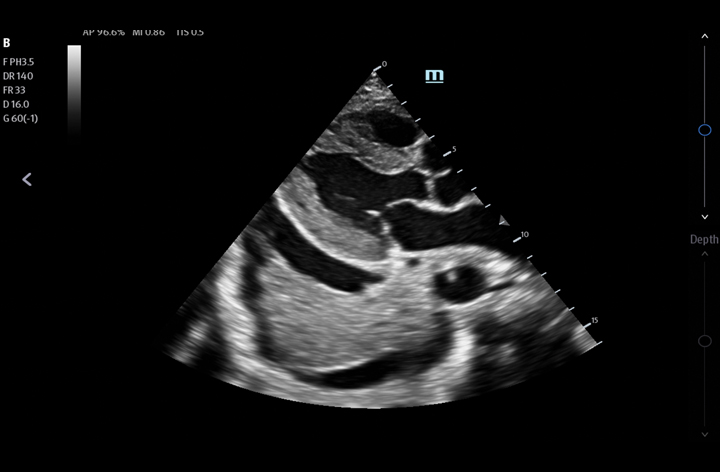

The TE7 Max Ultrasound System is designed to maximize your capabilities in demanding Point of Care environments. With its thoughtful industrial design and best-in-class image quality, the

TE7 Max provides a superior user experience during rapid clinical assessments and procedures taking place at the patient’s bedside

or on the go.

The TE7 Max boasts a large 21.5” vertically oriented high-definition display and a sealed touch-based interface to optimize visualization and accessibility when every second counts. The TE7 Max also incorporates a comprehensive suite of artificial intelligence (AI) powered Smart Tools and workflow enhancement software (iWorks™ Protocol) making efficiency and reproducibility the expectation for all end users.